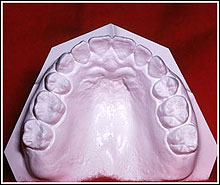

INTRAORAL Model